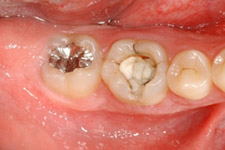

治療前:第一大臼歯が割れてしまっていて治療することが困難です。

第一大臼歯の抜歯後2週間で移植を行いました。

移植のために抜歯された右下の親知らず。歯根がまだ完成していない若い歯です。